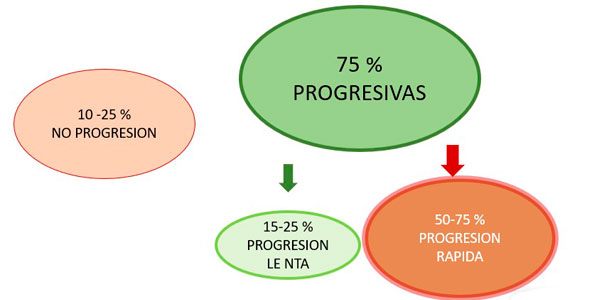

Escoliosis Congénita: Evolución:

En algunos casos las curvas no aumentaran y en otros casos se evidenciará un aumento progresivo de la deformidad.

El 75 % tienden a progresar, con frecuencia la cirugía precoz permite que el paciente evite una cirugía mucho más extensa más adelante.

Cuando su niño es diagnosticado de escoliosis congénita, es poco probable saber con exactitud que sucederá con su escoliosis.

Cada caso es diferente.

Algunos aumentarán más que otros.

Algunos casos progresaran rápidamente.

Y otros no tendrán mayores cambios.